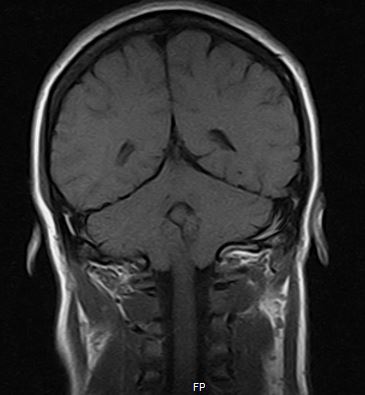

Simple, ignorant question (because I truly have no idea if this is normal or not). Does this rearview MRI of my brain show herniation or no? It seems obvious to me, but for all I know (and don't know), this may be normal

Thank you--that's my impression too, Emmaline; I was wondering if a Chiari can be visible from the rear as well. It seems clear to me from the rearview, but I'm not confident in that and was wondering what others thought.